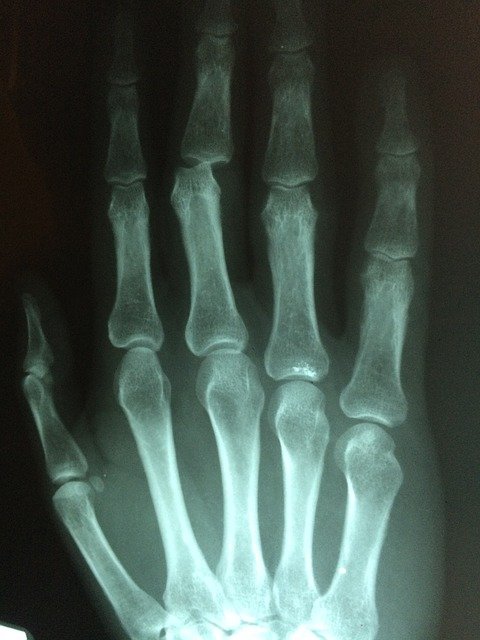

손가락 마디 통증 원인

손가락 마디 통증 원인 첫번째 손가락 건초염은 염증부위에 통증과 부종등이 나타납니다. 손가락에 힘을 주면 통증이 있고 손가락 마디가 제대로 펴지지 않는다거나 뻣뻣한 느낌을 받는 경우 손가락에 힘이 제대로 들어가지 않는 경우 등 여러 증상을 동반합니다. 손가락 건초염의 경우 대부분 사무직이나 손가락을 많이 사용하는 직업의 경우 고질병처럼 따라다니는 경우가 많습니다. 건초염의 원인으로는 손가락을 많이 사용해 건초가 손상되거나 세균 간염 통풍 등 여러 가지 원인으로 인해서 발생하게 됩니다.

손가락 마디 통증 원인 두 번째 퇴행성 관절염은 나이가 들면서 연골이 닳거나 손상 또는 퇴행성 변화로 관절을 이루는 뼈와 인대가 손상되어 염증이 생겨서 손가락 마디에 통증을 유발합니다. 대부분 나이가 들면서 많이 발생하는대요 연골이 오랜 세월 동안 닳아서 손상되기 때문에 노년층분들의 고질병중 하나로 꼽힙니다. 퇴행성 관절염의 경우 손가락 마디 통증에서 그치지 않고 무릎관절 팔꿈치 등 연골이 손상된 경우 통증을 느낍니다.

손가락 마디 통증 원인 세 번째 류마티스 관절염은 정확한 원인은 밝혀지지 않았지만 면역력 문제로 많이 발생한다고 알려져 있습니다. 다른 원인으로는 세균 감염 바이러스 등이 있습니다. 육체적으로 무리를 하거나 스트레스를 많이 받는 경우 발병률이 높아지는 것으로 알려져 있습니다. 증상으로는 피고 감 식욕부진 무력 감등이 있습니다. 류마티스 관절염의 경우 아침에 일어났을 때 관절염이 더 심해집니다. 손가락이 뻣뻣해지거나 통증이 1시간가량 지속되는 경우 류마티스 관절염이 의심되므로 필히 병원에 방문하여야 합니다. 방치할 경우 손가락에 변형이 생길 수 있습니다.